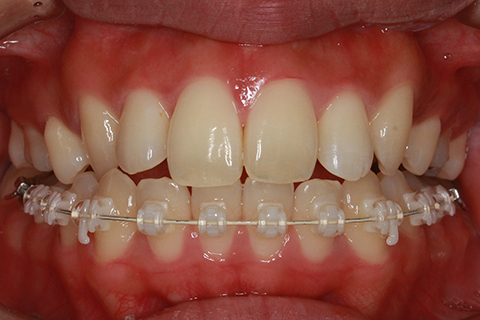

矯正期間18ヶ月

ハーフリンガル矯正2(上の歯のみ舌側矯正で治療)

治療前

治療中

治療後

- 年齢・性別

- 23歳女性

- 治療期間

- 1年6ヶ月

- 抜歯

- 上顎4番

- 治療費

- 110万円(税込み)

- 備考

- ハーフリンガル矯正

- 治療内容

- 上下前歯部凸凹の改善

- 施術の副作用(リスク)

- 裏側矯正の特性上、表側矯正と比較すると治療期間が長くかかる場合が多い。